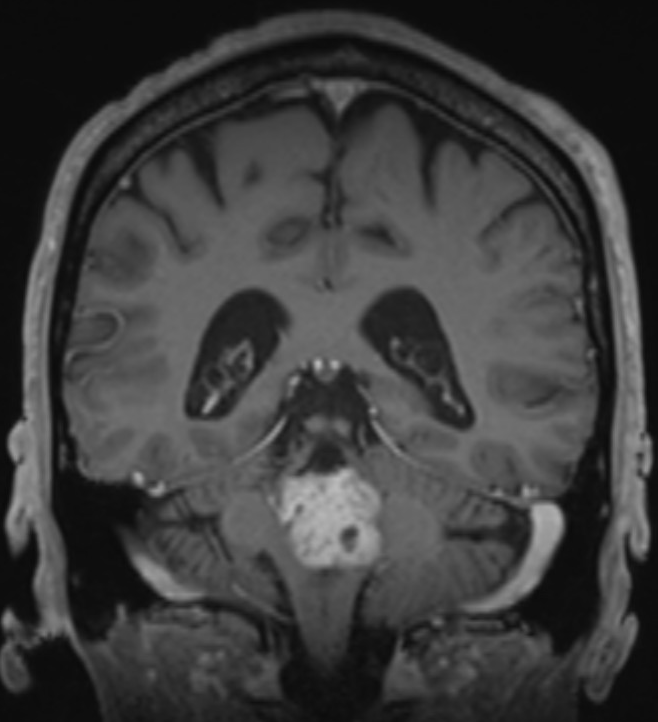

MRI image.png